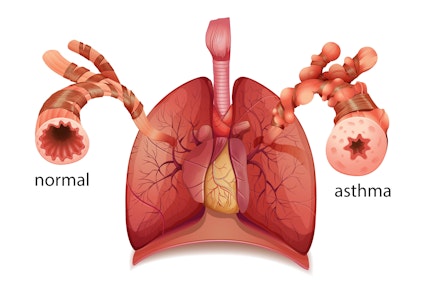

Asthma

Asthma is a chronic condition that causes the lungs and airways to become inflamed. It can affect patients of all ages, and it is often triggered during exercise. Those who suffer from asthma can experience a range of symptoms, including shortness of breath, wheezing, coughing, and tightness in the chest. Although symptoms are mild for many patients, others can experience life-threatening asthma attacks.